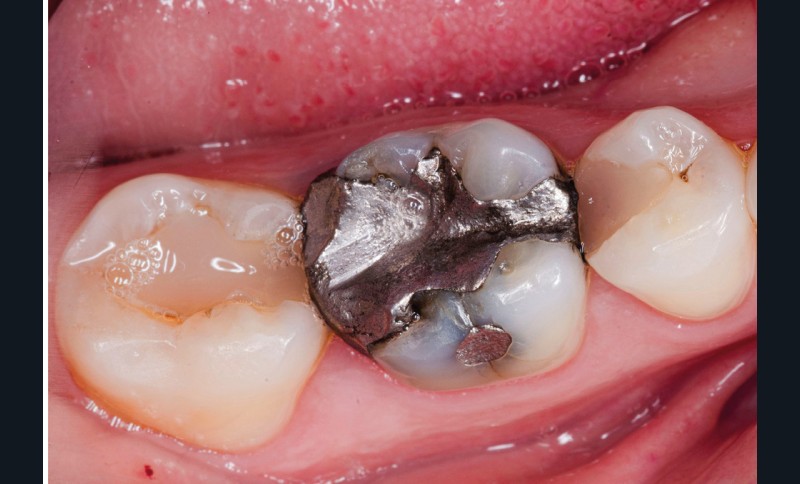

A l’examen clinique, nous observons une restauration à l’amalgame sur 46 non étanche ainsi que des restaurations composites sur 45 et 47 dont les morphologies sont usées (fig. 1). Après réalisation des tests cliniques, nous confirmons que la 46 est à l’origine de la sensibilité décrite par la patiente.